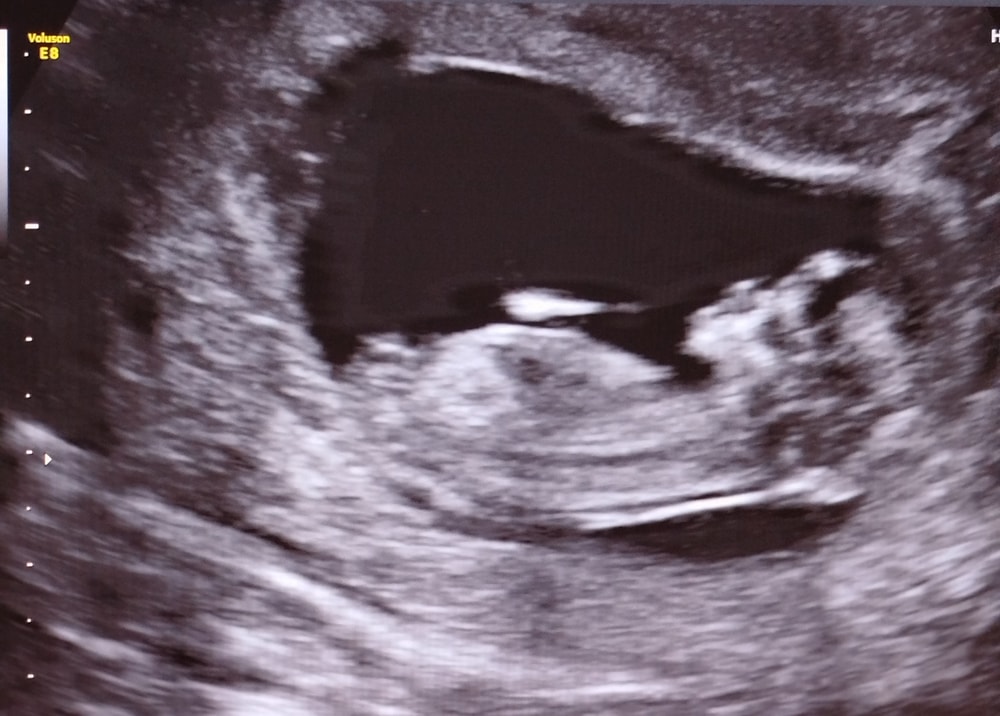

Половой бугорок🩷

УЗИ, КТГ, доплерБыла на 1 скрининге, предположили девочку, как думаете, мальчик или девочка? 🥰